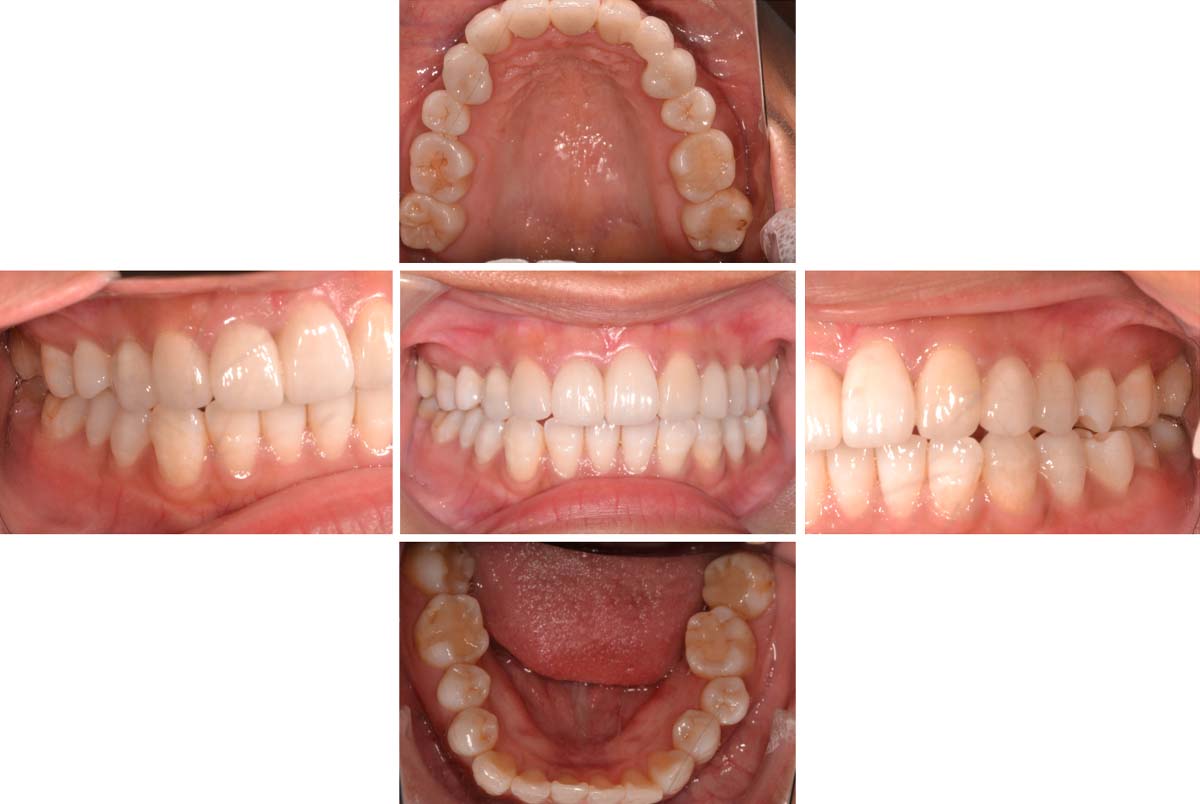

| 術後 |

|---|

![]() |

年齢:33歳

主訴:前歯の黒ずみがきになる。奥歯に穴が開いている気がする。

初診時の診断と治療方針

医療面接、レントゲンや写真より、歯並びの問題と将来的に噛み合わせから顎関節症状がでてくる恐れがあると診断できました。そのため、矯正治療を含めた咬合治療をしていくことになりました。